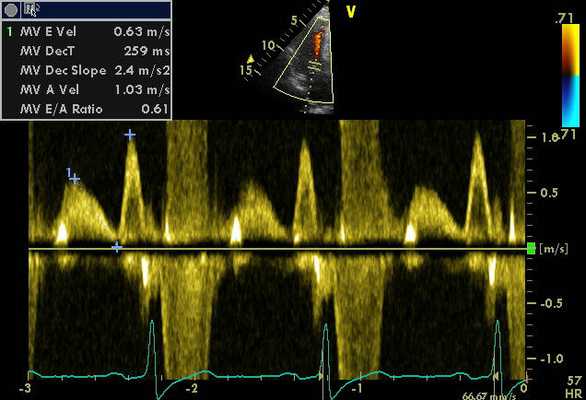

Методика импульсно-волновой ТД

Анализ продольного движения миокарда проводился в верхушечном 4-камерном срезе сердца с синхронной записью мониторного отведения ЭКГ при задержке дыхания пациента в течение 5-10 сердечных циклов (рис. 1). Контрольный объем (5x8 мм) ТД размещался в латеральной и медиальной частях фиброзного кольца митрального клапана (МФК). Точкой начала отсчета временных фаз считали зубец R ЭКГ. Проводился анализ параметров ТД от латеральной (МФКл) и медиальной (МФКм) частей фиброзного кольца митрального клапана: ТМРИ вычислялся по ТД в медиальной и латеральной частях МФК по графикам максимальной скорости движения МФК как отношение разницы временного интервала между началом положительной волны ИВС до начала «Еm» (a’) и временем систолической волны Sm (b’), по формуле:

Рис. 1. Принцип расчета ТМРИ по ТД фиброзного кольца митрального клапана.